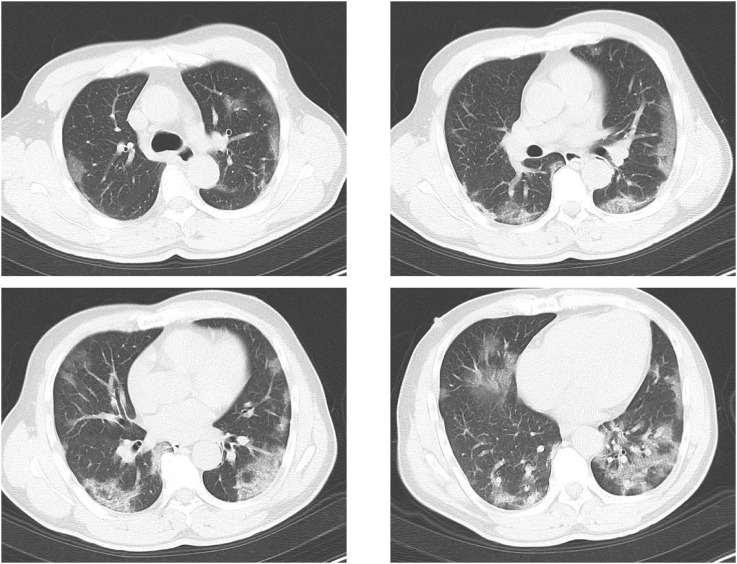

He came to our hospital on day 6. On physical examination, his vital signs were as follows: blood pressure, 102/78 mmHg; pulse, 96/min; respiratory rate, 32/min; oxygen saturation, 92% on room air; body temperature, 39.2 °C; and Glasgow Coma Scale (GCS), 15. White blood count (WBC) was 2650/μL (Neutro 72.4%, Lymph 23.4%), C-reactive protein (CRP) was 3.12 mg/mL. D-dimer was 1.3 μg/mL (normal range < 1 μg/mL). His computed tomography (CT) images showed ground glass opacity on both lungs (Fig. 1 ). RT-PCR test of the nasal specimen showed the positive result of SARS-CoV-2.

Fig. 1.

CT images on admission (day 6 from onset). Computed tomography (CT) images showed typical ground glass opacity on both lungs.